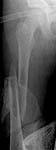

Date: Wed, 20 Jun 2001 23:19:13 -0700

From: Carlo Bellabarba

alex,

here's a recent Ender example with three-month followup. sorry about the

quality of the injury image--there were better outside films that have since

disappeared. I still think this technique is useful, even in rotationally

unstable patterns such as this one. i take the nails out at 6 mos, and leave

them a little proud on purpose (this 10 year-old is a bit of chunkster so

they don't bother him) and suture them down so that they don't back out

more.

it aren't fancy, but it's quick and seems to work.

carlo bellabarba